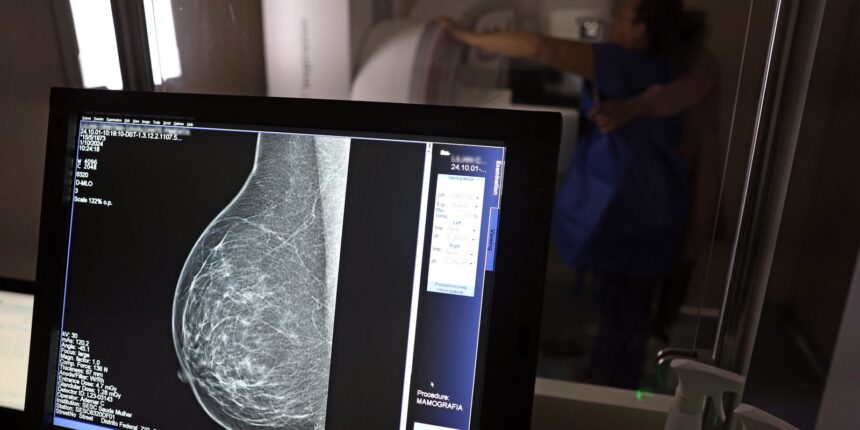

No Outubro Rosa, o Instituto Nacional de Câncer (Inca) estimou 73.610 novos casos este ano no país. É o câncer que mais mata mulheres no Brasil. As mulheres em tratamento pela doença têm o direito de receber o auxílio-doença ou o benefício de prestação continuada.![]()

A vice-presidente da Comissão de Previdência Social Pública da Ordem dos Advogados do Brasil do Rio de Janeiro (OAB-RJ), Danielle Guimarães, destaca que o câncer de mama é uma das doenças que mais afetam mulheres no Brasil, impactando não apenas a saúde física e emocional, mas também a capacidade de trabalho e a segurança financeira das pacientes.